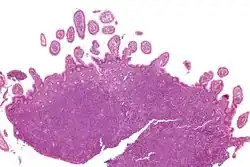

Micrograph of terminal ileum with mantle cell lymphoma (bottom of image). H&E stain.

Micrograph showing mantle cell lymphoma (bottom of image) in a biopsy of the terminal ileum. H&E stain.